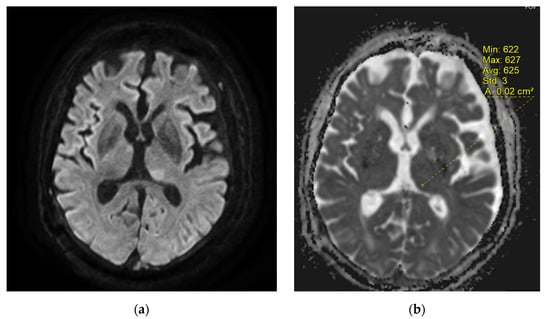

2. Case Report